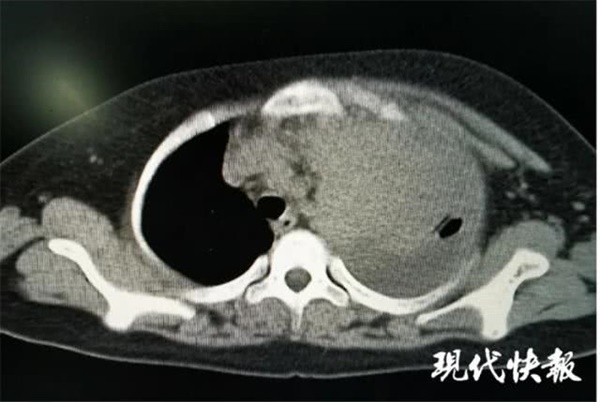

Kết quả chụp CT phổi của Tiểu Kiệt.

Dựa trên kết quả chụp phim, bác sĩ nhận ra toàn bộ lá phổi trái của Tiểu Kiệt biến mất, nó bao phủ bởi một khối mật rất lớn. Thậm chí cả tim, khí quản và một số cơ quan khác bị ép sang bên phải, đường phân chia không còn rõ ràng. Khi cậu bé nằm xuống, ngực bên trái nhô cao hơn bên ngực phải 1cm.

Ngày 21/4, mẹ của Tiểu Kiệt đã dẫn con trai tới Bệnh viện Nam Thông để làm thêm các xét nghiệm. Kết quả chụp CT ngực cho thấy có một lớp vảy phân bố không đều trong khoang ngực trái, dịch tràn ra cả màng tim. Ngày 23/4, chụp PET/CT cho thấy có một khối mật độ mô mềm lớn 18,8cm được nhìn thấy trên khoang ngực trái. Bác sĩ cho biết khả năng khối u ác tính có bắt nguồn từ màng phổi trái. Khi nghe thấy kết quả như vậy, cả gia đình Tiểu Kiệt không thể tin vào tai mình.